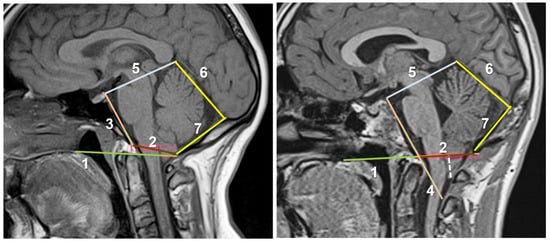

- McRae’s line (McRL). McRae’s and McGregor’s lines were described in the late 1940s to assess basilar impression in plain radiographs [102,103]. In 1953, McRae used Chamberlain’s line to evaluate different bony abnormalities in the FM region [103]; however, in a second paper, studying the occipitalization of the atlas, he defined the McRL, which has been extensively used in many studies to describe the position of the normal odontoid peg and/or cerebellar tonsils [102,103]. This line is drawn from the basion to the opisthion and represents the planum of the FM, and its length the anteroposterior width of the FM (Figure 7, line 2). In most studies and clinical practice, TH is evaluated by measuring the distance from the most caudal aspect of the tonsils to a line running perpendicular to the McRL [6,99]. However, since TH is usually asymmetrical, coronal slices are the best method to measure and evaluate it. As indicated by Raybaud and Jallo, in normal individuals, both the McRae and Chamberlain lines are superimposed but diverge when the clivus is hypoplastic [6] (Figure 8).

- Clival and Wackenheim lines. The clival line is the distance between the top of the dorsum sellae and the basion and is a measure of clivus length [6,25]. If the line is extended postero-inferiorly to the upper cervical canal, it forms the Wackenheim line, which is usually tangential to the posterior margin of the odontoid tip (Figure 8, lines 3 and 4).

- Incisural line. This line is drawn from the tip of the dorsum sellae to the union of the vein of Galen with the straight sinus. Its length is equivalent to the antero-posterior length of the tentorial notch (Figure 8, line 5).

- Supraoccipital line. This line is drawn from the internal occipital protuberance to the opisthion and represents the length of the supraocciput (Figure 8, line 7).